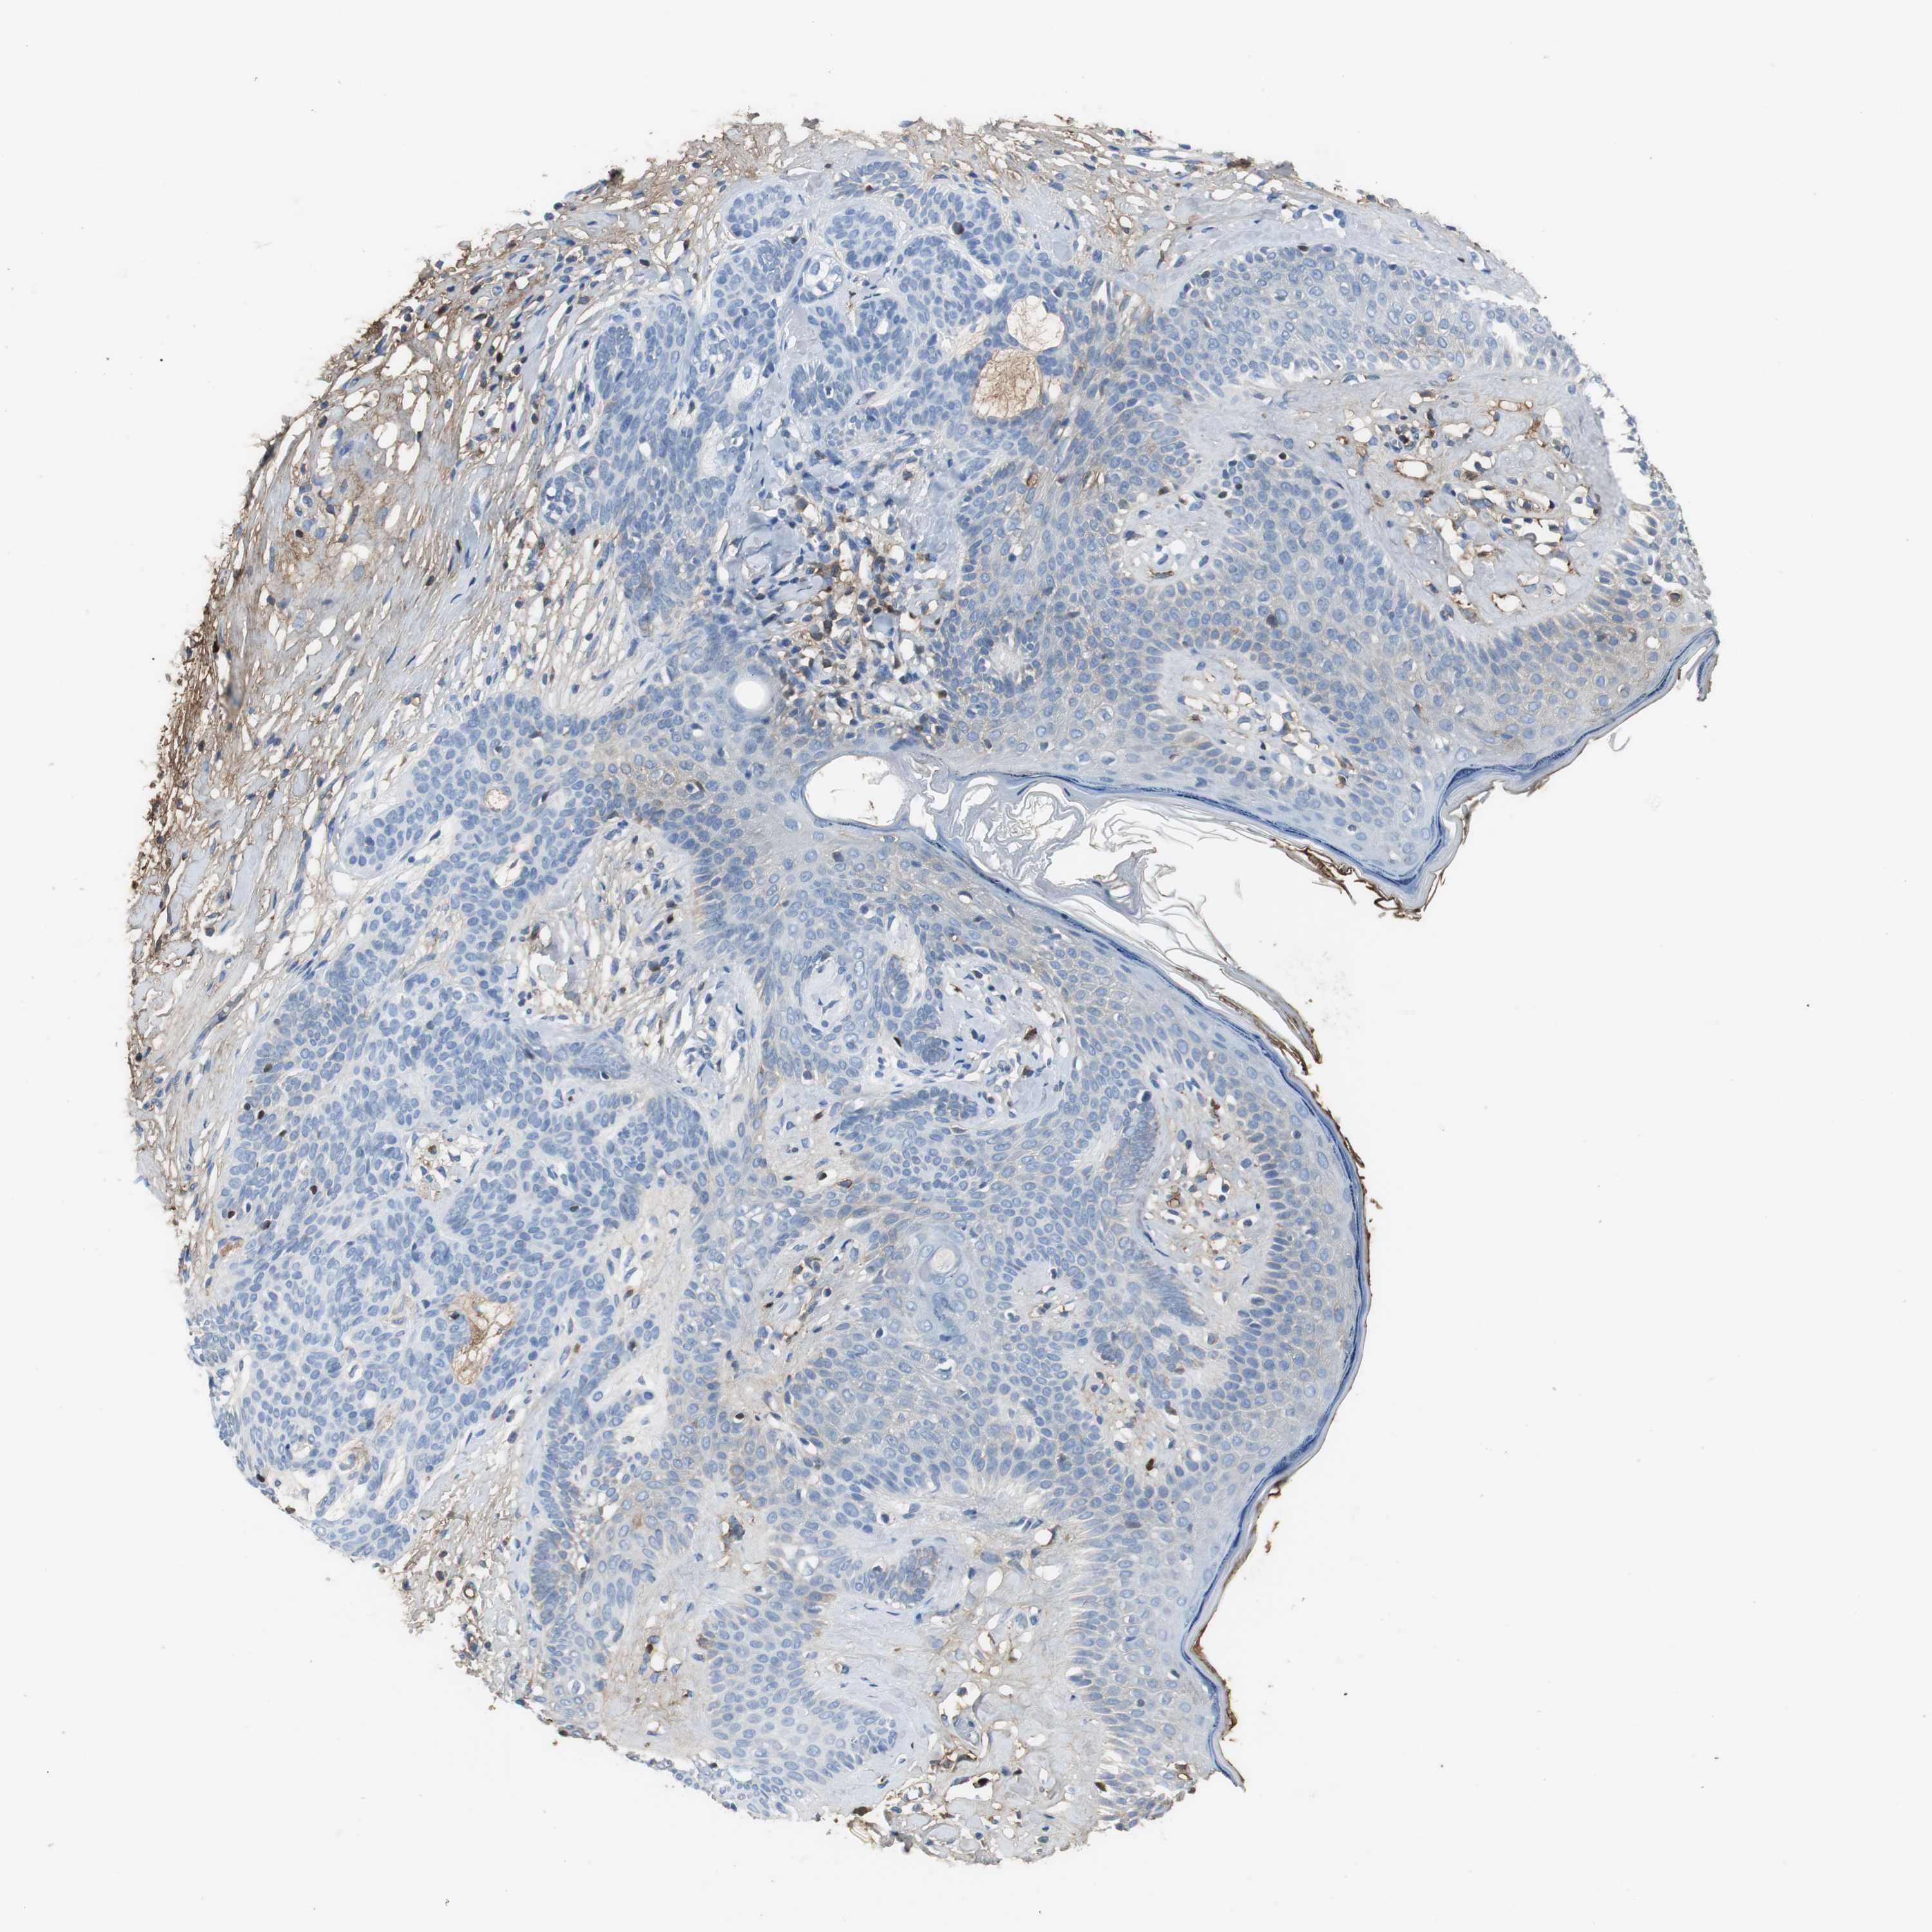

SKIN CANCER - Protein expressioni

A mouse-over function shows sample information and annotation data. Click on an image to view it in a full screen mode. Samples can be filtered based on level of antibody staining by selecting one or several of the following categories: high, medium, low and not detected. The assay and annotation is described here.

Antibody staining in the annotated cell types in the current human tissue is reported as not detected, low, medium, or high, based on conventional immunohistochemistry profiling in selected tissues. This score is based on the combination of the staining intensity and fraction of stained cells.

Each image is clickable and will lead to virtual microscopy that enables deeper exploration of all samples and also displays staining intensity scores, fraction scores and subcellular localization as well as patient and tissue information for each sample.

Antibody HPA001217

Antibody HPA006013

Staining

High

Medium

Low

Not detected

Intensity

Strong

Moderate

Weak

Negative

Quantity

>75%

75%-25%

<25%

None

Location

Nuclear

Cytoplasmic/membranous

Cytoplasmic/membranous,nuclear

Squamous cell carcinoma, NOS

Basal cell carcinoma